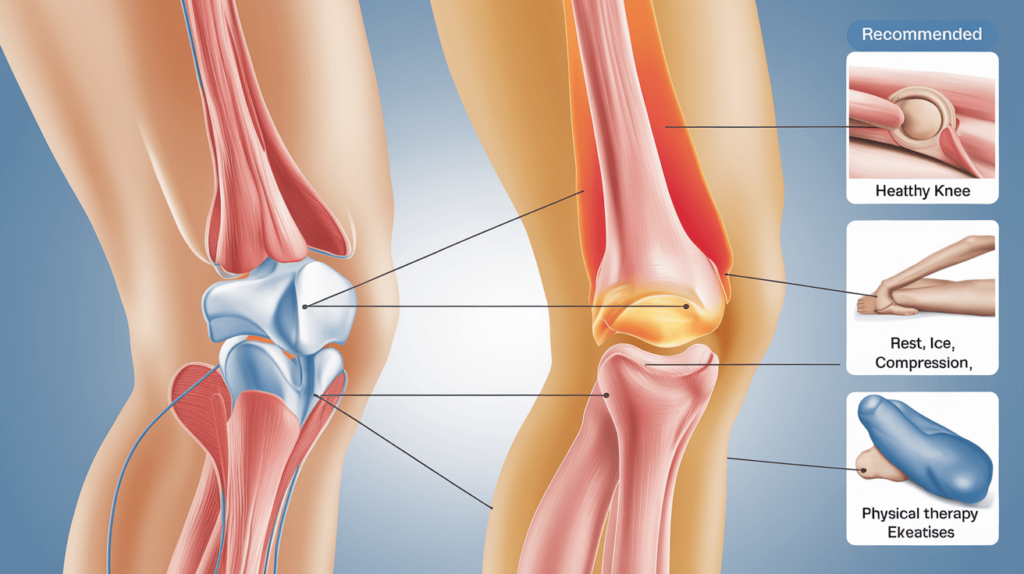

Akhir sekali, kita akan membincangkan langkah-langkah yang boleh diambil untuk mengatasi masalah sakit lutut tak boleh bengkok. Ini termasuk rehat, penggunaan kaedah R.I.C.E, fisioterapi, dan latihan penguatan otot. Dengan mengikuti langkah-langkah ini, anda dapat menguruskan keadaan lutut anda dengan lebih baik dan kembali kepada aktiviti yang anda cintai dengan selesa. Dengan pemahaman yang mendalam tentang punca, tanda, dan rawatan, anda akan lebih bersedia untuk menghadapi cabaran yang mungkin timbul akibat sakit lutut tak boleh bengkok.

2. Kaedah R.I.C.E

Kaedah R.I.C.E (Rehat, Ais, Kompresi, Elevasi) adalah teknik yang berkesan untuk menguruskan sakit lutut tak boleh bengkok (Sumber: https://www.jomkitalari.com/rawat-kecederaan-dengan-prinsip-r-i-c-e/). Menggunakan pek ais pada lutut yang sakit selama 15-20 minit setiap beberapa jam dapat membantu mengurangkan bengkak dan kesakitan. Ais berfungsi untuk mengecilkan saluran darah, yang seterusnya mengurangkan aliran darah ke kawasan yang terjejas. Selain itu, menggunakan pembalut elastik untuk memberikan kompresi pada lutut dapat membantu mengekalkan tekanan dan mengurangkan bengkak. Elevasi lutut dengan meletakkannya di atas bantal atau permukaan yang lebih tinggi juga dapat membantu mengurangkan bengkak dengan memudahkan pengaliran cecair dari kawasan yang terjejas. Dengan menggunakan kaedah R.I.C.E secara konsisten, anda dapat menguruskan sakit lutut tak boleh bengkok dengan lebih berkesan.

3. Fisioterapi

Fisioterapi adalah salah satu rawatan yang berkesan untuk sakit lutut tak boleh bengkok. Fisioterapis dapat membantu merancang program pemulihan yang sesuai berdasarkan keadaan lutut anda. Mereka akan melakukan penilaian menyeluruh untuk mengenal pasti punca kesakitan dan merancang latihan penguatan otot yang dapat membantu mengurangkan risiko kecederaan di masa hadapan. Sebagai contoh, fisioterapis mungkin akan mencadangkan latihan regangan dan penguatan yang khusus untuk otot-otot di sekitar lutut, membantu meningkatkan kekuatan dan fleksibiliti. Dengan mengikuti program fisioterapi yang disyorkan, anda dapat mempercepatkan proses pemulihan dan kembali ke aktiviti harian dengan lebih cepat.